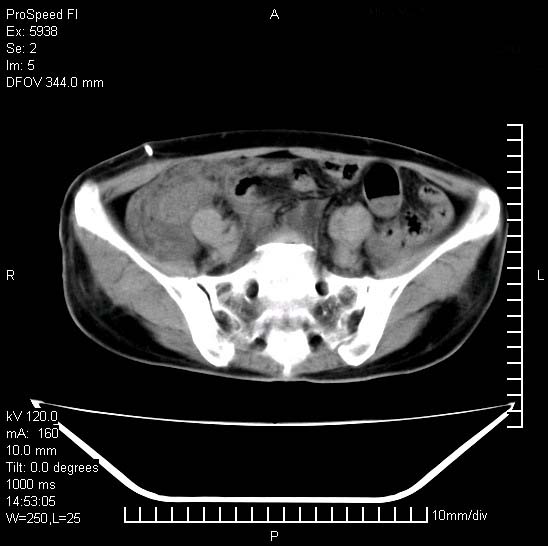

反复小腹疼痛,盆腔积液3年,无发热,曾抗痨一段时间。

右下腹肠管壁增厚,边缘有侵润改变及点状低密度影,内侧可见局限性肿块。考虑-----淋巴瘤或增生型肠结核----盆腔积液-----建议肠镜检查

考虑盆腔及右下腹感染性病变(结核可能)。

结核性腹膜炎伴积液。右侧髂骨骨窗看看,是否有骨质破坏。

提示结核性腹膜炎合并盆腔积液。建议查ppd或tb抗体。